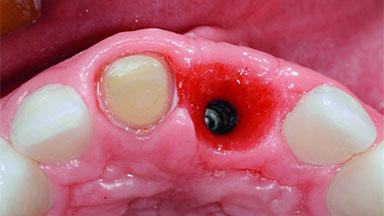

| # of Implants | 1 |

| Type of Implants | Two-Piece |

| Attachment | Two-Piece |

| Bone Volume | Deficient horizontally, requiring prior grafting |